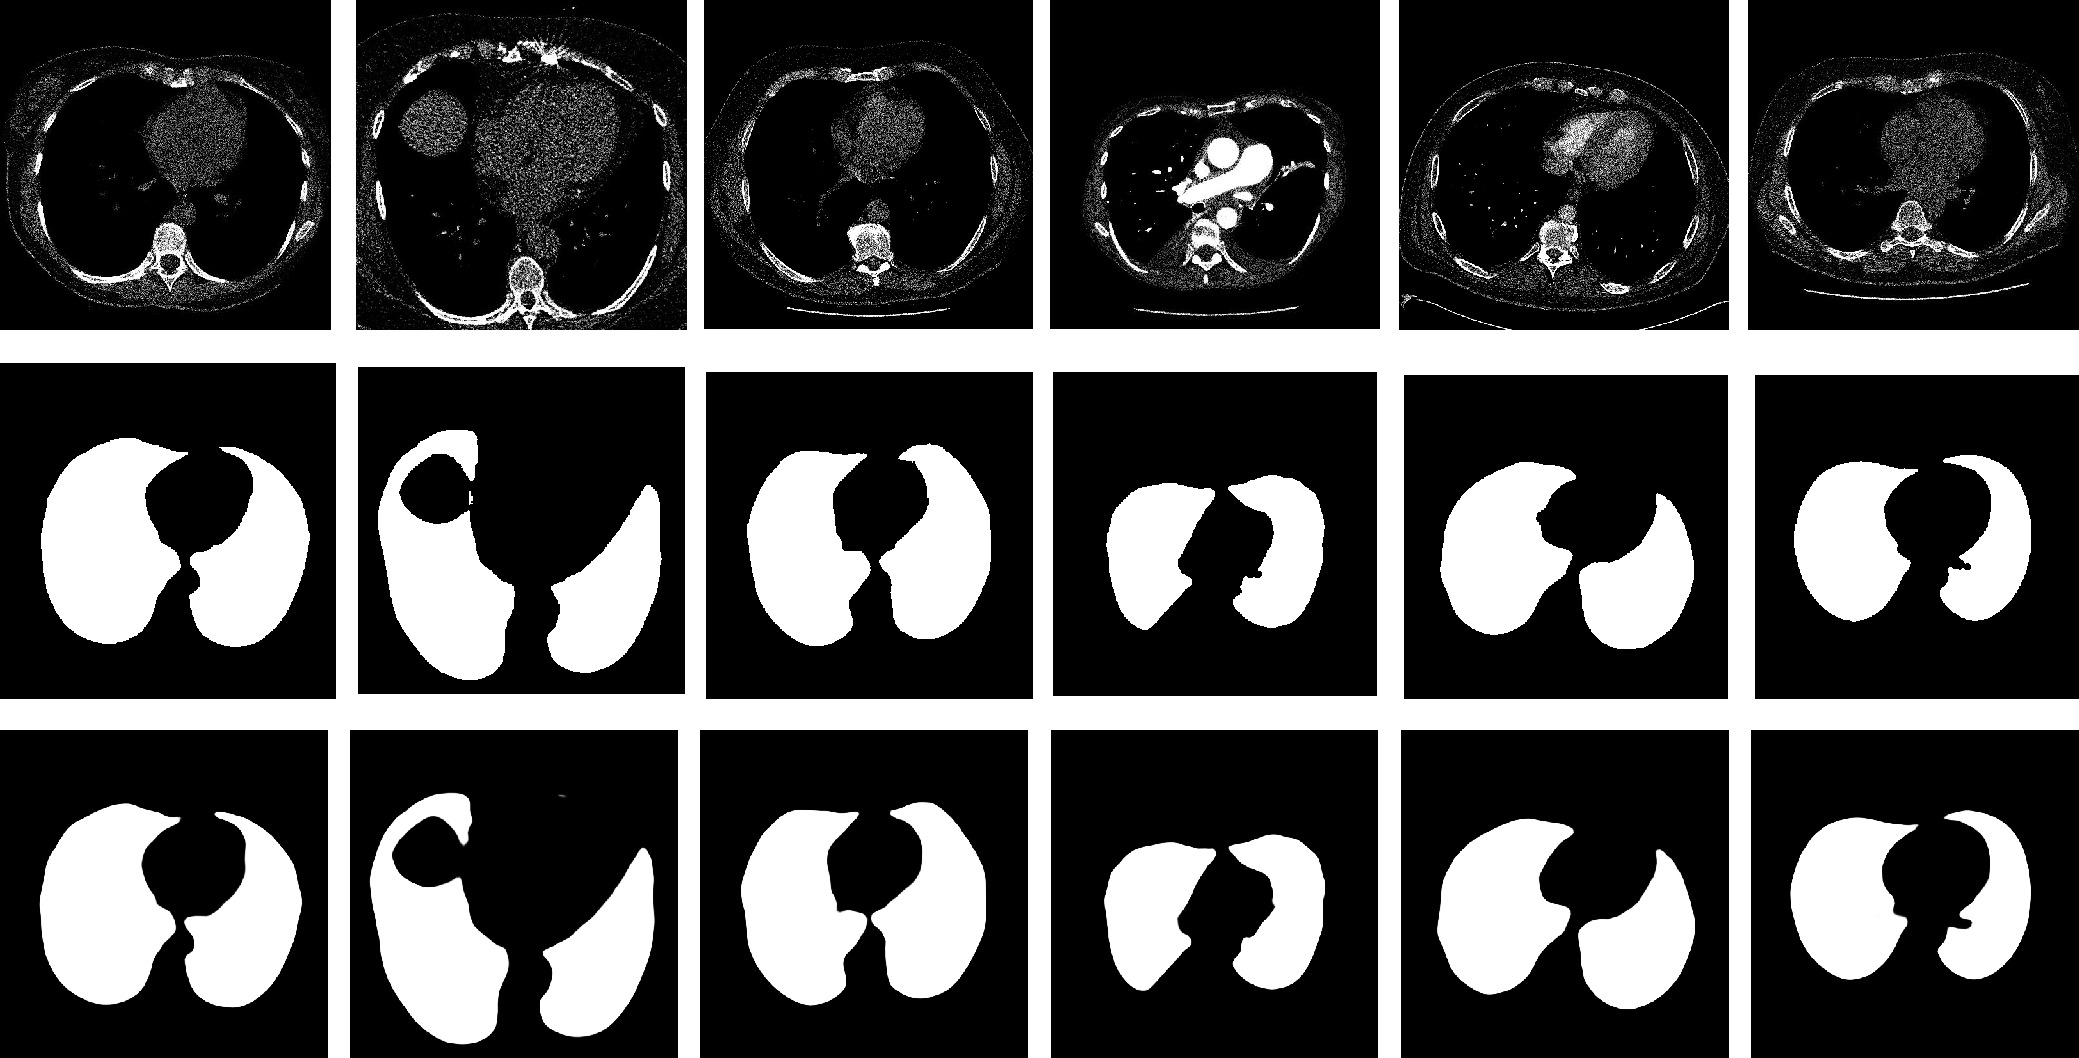

MFAINet: Multi-Receptive Field Feature Fusion With Attention-Integrated for Polyp Segmentation

Guangzu Lv, Bin Wang, Cunlu Xu, Weiping Ding, Jun Liu

2026, 13(4): 822-836. doi: 10.1109/JAS.2025.125408

Abstract(1489) HTML (138) PDF(76)

Abstract:

Colorectal cancer has become a global public health concern. Removing polyps before they become malignant can effectively prevent the onset of colorectal cancer. Currently, multi-receptive field feature extraction and attention mechanisms have achieved significant success in polyp segmentation. However, how to effectively fuse these mechanisms and fully leverage their respective strengths remains an open problem. In this paper, we propose a polyp segmentation network, MFAINet. We design an attention-integrated multi-receptive field feature extraction module (AMFE), which uses layering and multiple weightings to fuse the multi-receptive field feature extraction and attention mechanisms, maximizing the extraction of both global and detailed information from the image. To ensure that the input to AMFE contains richer target feature information, we introduce a multi-layer progressive fusion module (MPF). MPF progressively merges features at each layer, fully integrating contextual information. Finally, we employ the selective fusion module (SFM) to combine the high-level features produced by AMFE, resulting in an accurate polyp segmentation map. To evaluate the learning and generalization capabilities of MFAINet, we conduct experiments on five widely-used public polyp datasets using four evaluation metrics. Notably, our model achieves the best results in nearly all cases.